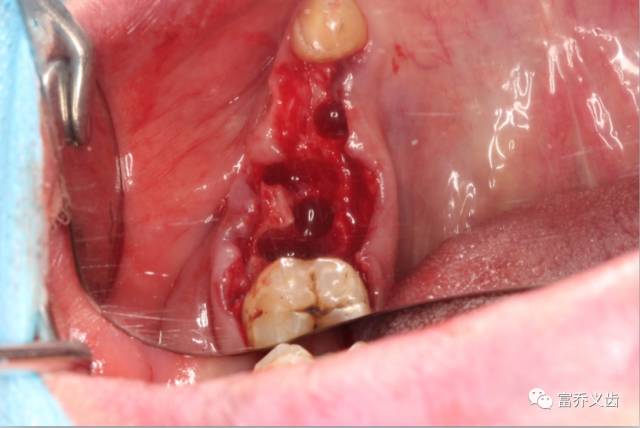

拔除46牙根

备洞完成,拔除牙根后